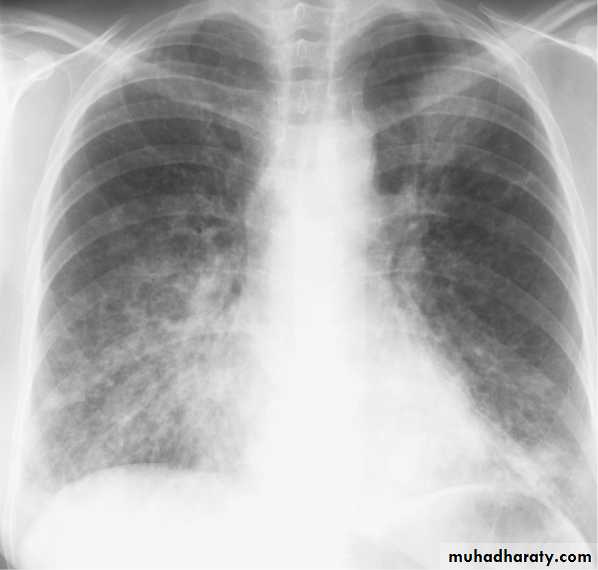

• Alveoiar oedema (‘Bat’s wings’)

• Kerlev B lines (interstitial oedema)• Prominent upper lobe vessels

• Cardiomegaiy

• Pleura

• effusionKerley A lines (Arrows), Kerley B lines (arrowheads)